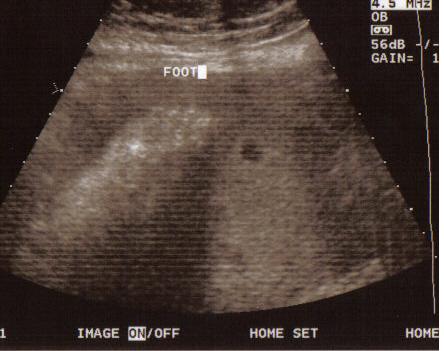

These are the last pictures of the baby until I actually get to hold him/her. We had our 37w check up and a sonogram. Everything looks great. Baby is measuring in the 50th percentile and approx. 6lbs 9oz. Image Attachment(s):